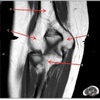

46

What is letter A?

TRICEPS MUSCLE

47

What is letter B?

TRICEPS TENDON

48

What is letter C?

FATTY TISSUE

49

What is letter D?

OLECRANON

50

MEDIAL EPICONDYLE

51

ULNA

52

LATERAL EPICONDYLE

53

HUMERUS

54

55

COMMON FLEXOR TENDON

56

RADIAL TUBEROSITY

57

RADIAL HEAD

58

59

ANCONEUS MUSCLE

60

61

62

TRICEPS

63

64

CORONOID PROCESS

65

TROCHLEA

66

What is letter E?

BRACHIALIS